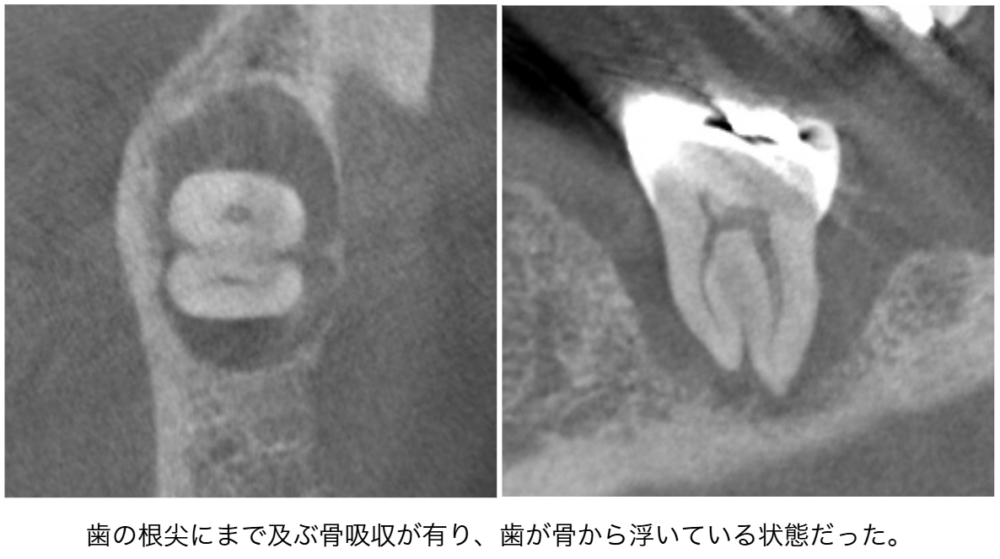

| 来院時の主訴 | 「歯がグラグラする。噛むと痛い。」 |

| 医院の診断 | 重度の歯周病 |

| ここがこだわりのポイント!☝ | 根尖にまで及ぶ歯周病がありましたが、綿密な術前検査で神経を残せる可能性があったため神経を残して治療しました。術前検査で歯の周囲に4〜11mmの歯周ポケットがありましたが全周3mm以下に改善しました。健康な歯周組織(骨・歯肉)を獲得することができ、患者様の主訴である歯の揺れもなくすことができました。 |